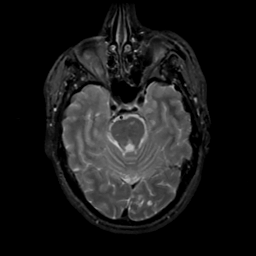

MR Study #10, April 28, 1991 -- Slice #16

[Home][Help][Clinical][Tour 1][Tour 2] Slice 16